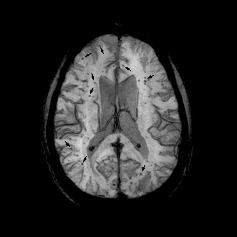

Bleeding in the brain, identified as cerebral microbleeds (CMB) on magnetic resonance imaging (MRI), are tiny deposits of blood in the brain that are associated with increasing age, cerebrovascular diseases, hypertension, and chronic kidney disease. CMBs are a common cause of cognitive decline and contribute to risk of stroke. Using MRI, cerebral microbleeds are found in nearly 20 percent of people by age 60, and nearly 40 percent of people by age 80. Direct examination of human brain tissue samples shows that brain bleeding is almost universal by age 70.